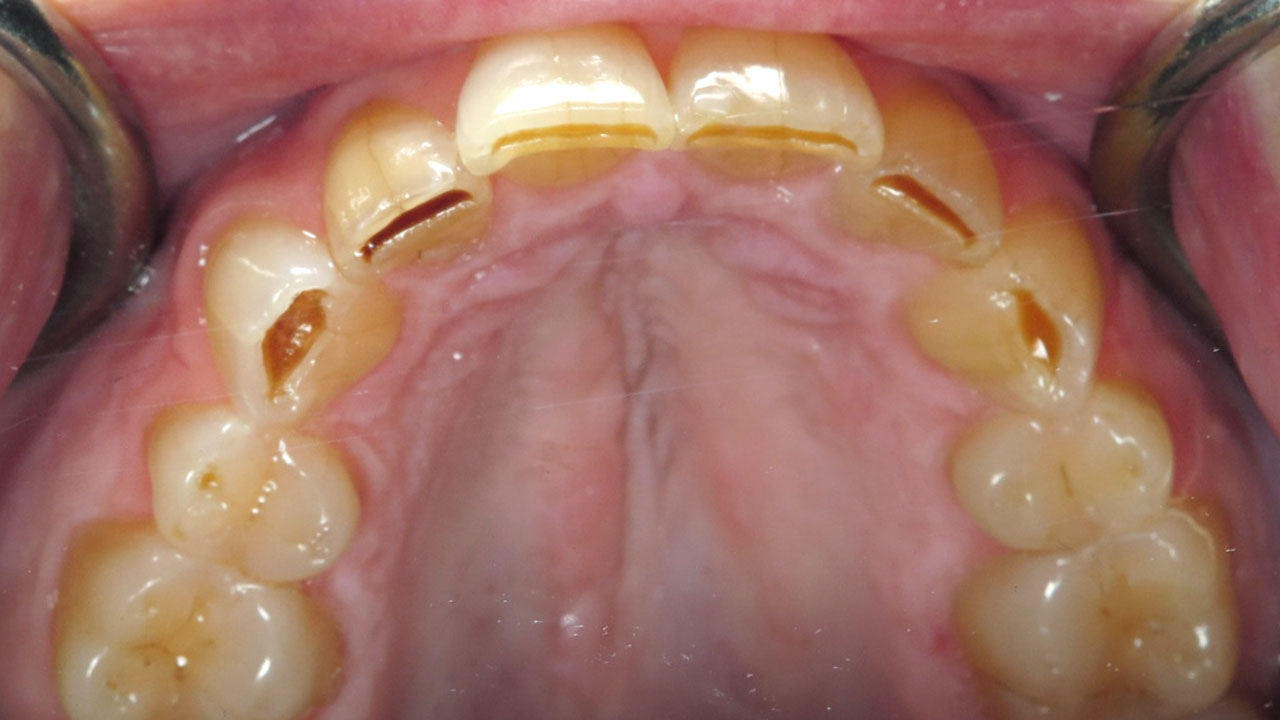

The patient noticed that her front teeth had become sharp and were catching her tongue and lip. She had also noticed darker areas developing near the edges of her upper front teeth. She was aware that she grinds her teeth and already wore a nightguard.

This patient came to the office because her front teeth had begun to feel sharp and were catching her tongue and lip during normal function. She had also noticed darker areas forming near the edges of her upper front teeth.

The patient was aware that she grinds her teeth and had been wearing a nightguard. Over time, the grinding had worn through the protective enamel on the edges of several teeth, exposing the underlying dentin. In some areas, early decay had begun to develop within the exposed dentin.